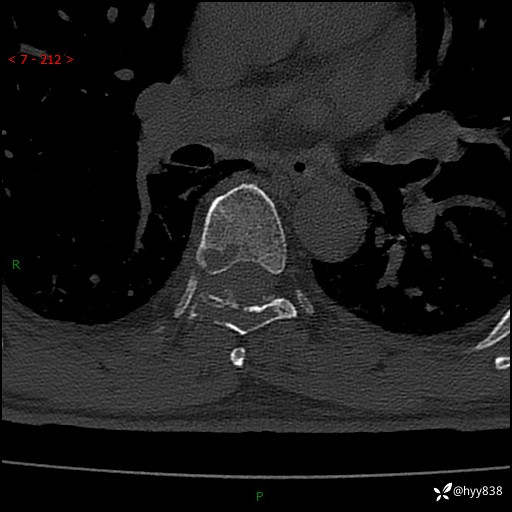

胸椎CT平扫(骨窗+软组织窗)